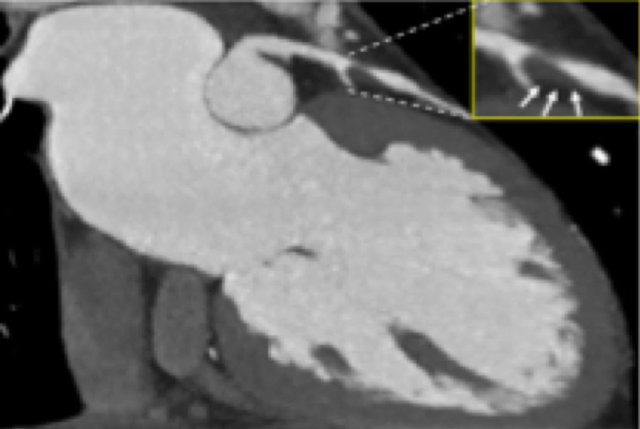

The findings are:

- The total calcium score of 0 indicates the absence of calcified plaque in the coronary tree.

- Severe stenosis (70-99%) in the mid LAD and D2 branch.

Continue with the next images of the same patient...

Same patient. First, study the CTA image.

How would you describe the findings?

The coronal image shows a central low-attenuation area around the lumen

of the LAD.

This low-attenuation area is surrounded by a higher attenuation

area.

This finding is the earlier discussed napkin-ring sign, which is a high-risk

plaque feature.

This patient classifies as CAD-RADS 4A/P1/HRP.